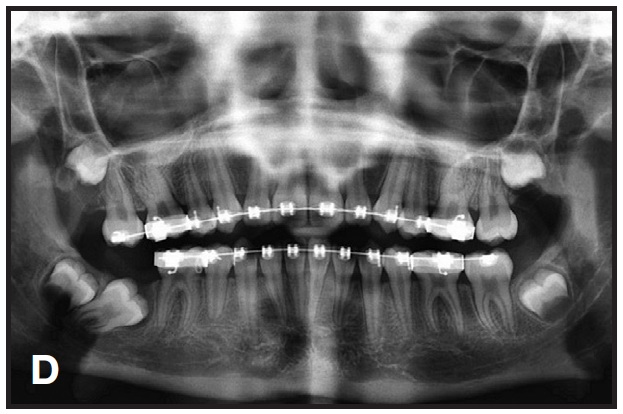

This technique is demonstrated in a 13-year-old female patient with an impacted lower right second molar (D). A U-loop spring was activated after surgical exposure of the tooth (E). Two months later, the second molar had been partially uprighted (F). After three more months of uprighting, the spring was removed and a continuous archwire was placed (G). It took another three months to completely upright the molar using straightwire mechanics, with no side effects on the anchor units (H).